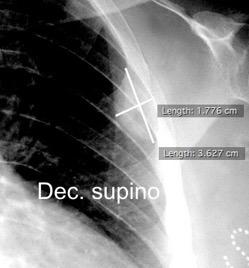

Signos en decúbito supino

175 cc

Dec. supino